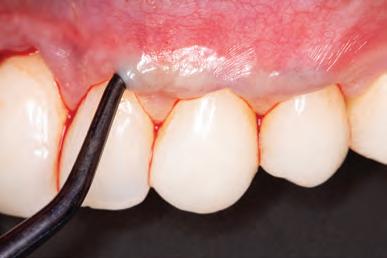

Surgical considerations

New parameters of restorative therapy require consideration of esthetic results that might require both periodontal and operative procedures to restore a harmonious integration and an esthetic balance of gingiva and tooth.34 Thus, periodontal plastic surgery procedures should be part of the clinician’s recipe for restoring the dentogingival complex. Traditionally, restorative therapy of teeth with gingival recession and carious or noncarious lesions has been achieved through operative procedures, with little attention given to the overall esthetic picture. In contrast, the perioesthetic approach considers the harmonious integration and interrelationship of the gingiva and tooth complex.35

In general, most clinical situations that present with gingival recession also involve a deficiency of keratinized attached gingiva, which requires mucogingival surgery.35 The periodontal plastic surgery procedures available for the treatment and correction of gingival recession include free gingival autografts, subepithelial connective tissue grafts, coronally positioned flaps, guided tissue regeneration, and acellular matrix grafts.36–41 These soft tissue grafts are indicated for the restoration of noncarious and carious cervical radicular lesions and for previously placed restorations associated with gingival recession. Recent advances in periodontal plastic surgery procedures have stimulated reassessment of the envelope technique and its modified version, the tunnel technique, for root coverage of single and multiple adjacent gingival recessions.36,42,43

The envelope technique originated in 1985 for single gingival recession defects.36,44 This procedure involved vertical incisions on either side of a tunnel preparation that

enabled placement of a subepithelial connective tissue graft within the tunnel to cover the gingival recession. The modified microsurgical technique eliminates the vertical incisions and allows the construction of a tunnel under the gingival tissue by means of a sulcular incision beyond the mucogingival line without raising a flap. This alteration of technique by using newly developed microsurgical instruments allows an undermining split-flap preparation of the facial tissues, ensuring improved blood supply, early wound healing, predictable root coverage, and esthetic postoperative results.45–53 This modified microsurgical approach simplifies the technique and allows for the treatment of multiple adjacent gingival recession defects in one surgical visit.

invasive preparationless procedure or with less conservative veneer preparations. The restorative materials discussed included injectable resin composites and ceramic (ie, feldspathic, pressable, machinable). For an optimal biologic framework and health, it was determined that connective tissue grafting would be necessary for treatment of the recessiontype defects on the maxillary left central and lateral incisors, canine, and premolars. The patient opted for the conservative preparationless composite veneers using the injectable resin technique followed by a connective tissue surgical procedure using the tunneling technique.